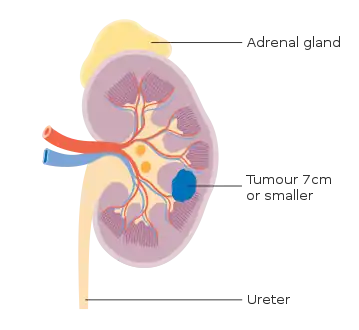

Staging is the process that helps determine the extent and spread of the disease.[45] Renal cell carcinoma is the only type of kidney cancer that can be staged. The first step of staging follows the TNM staging system proposed by the Union International Contre le Cancer that is widely used among cancers in other organs.[15] The TNM staging system classifies the primary tumor (T), lymph nodes (N) and distant metastasis (M) of the disease. The American Joint Committee on Cancer (AJCC) published a Cancer Staging Manual revision in 2010 that describes the values of TMN for renal cell carcinoma.[46][15]

The primary tumor of renal cell carcinoma is categorized in the table below, as according to the AJCC 8th Edition Cancer Staging Manual:[47][48]

| I | T1, N0, M0 | Tumor ≤7 cm; limited to kidney |

| T1a, N0, M0 | Tumor ≤4 cm; limited to kidney | |

| T1b, N0, M0 | Tumor 4-≤7 cm; limited to kidney | |

Stage 1 kidney cancer

Stage 1 kidney cancer Stage 2 kidney cancer